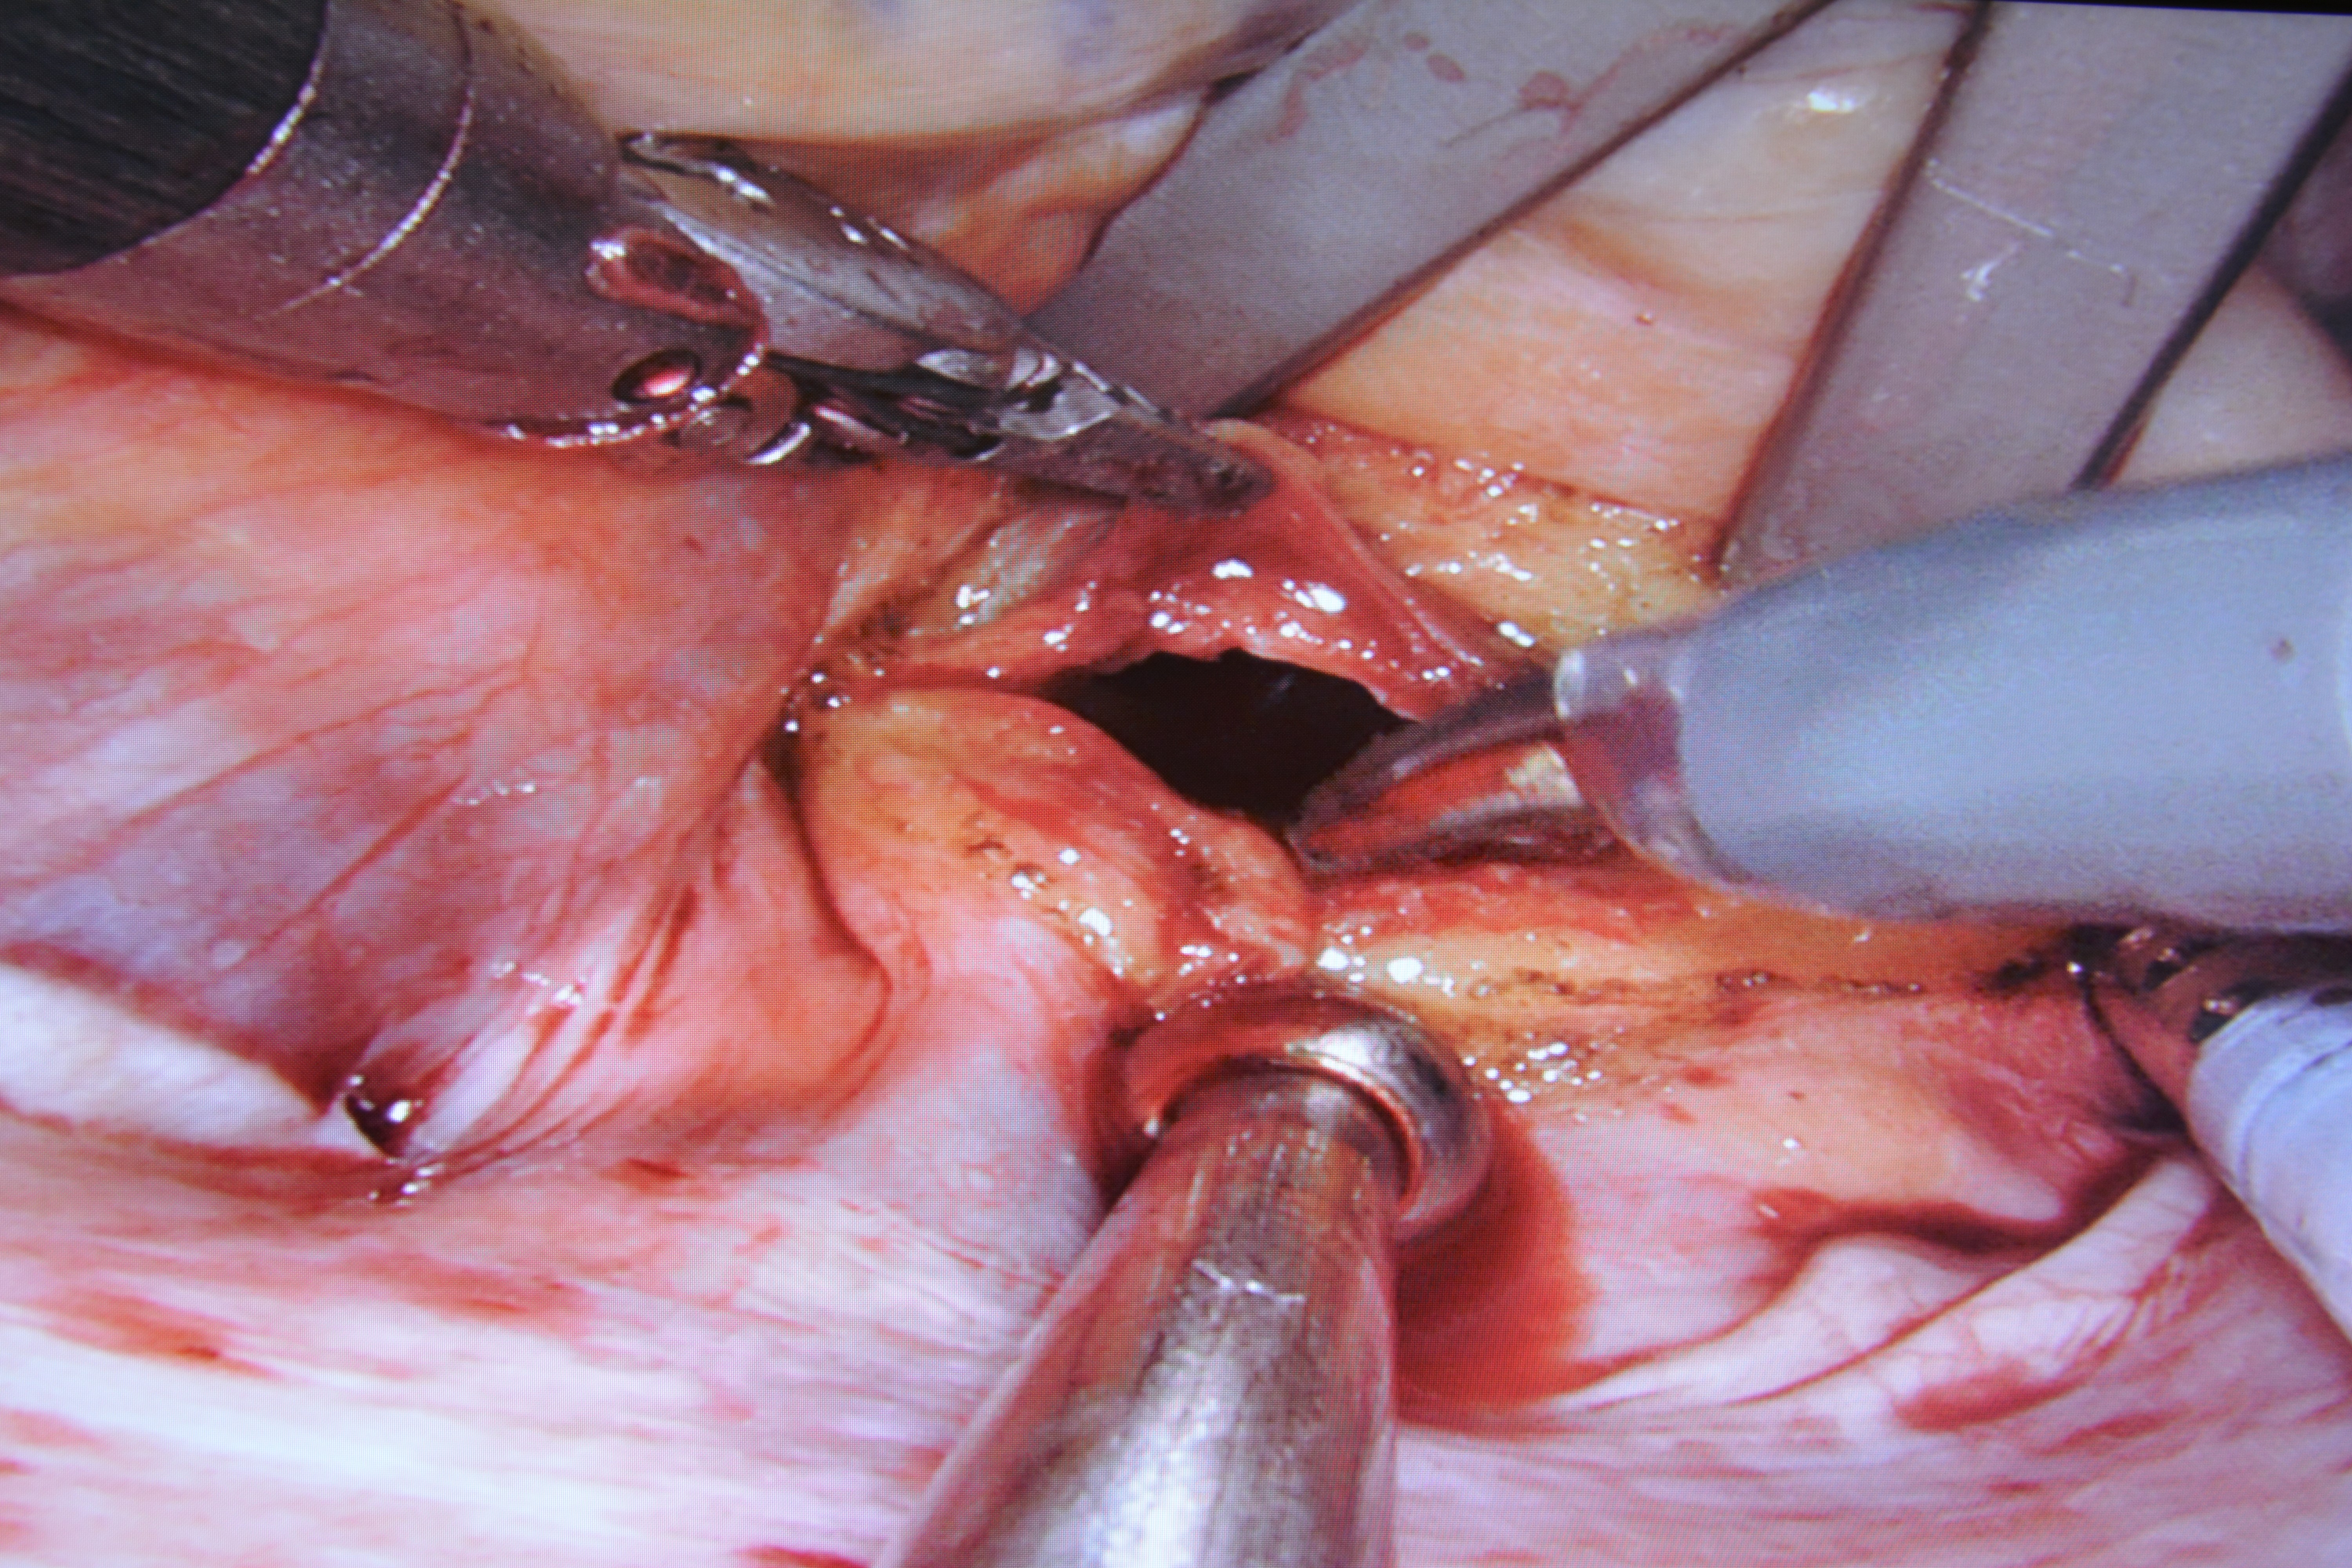

Dnia 09.08.2021r w Centralnym Szpitalu Klinicznym MSWiA, prof. dr hab. n. med. Piotr Suwalski wraz zespołem usunął guz serca i zaszył ubytek w przegrodzie serca za pomocą robota da Vinci. Była to pierwsza taka operacja w Polsce.